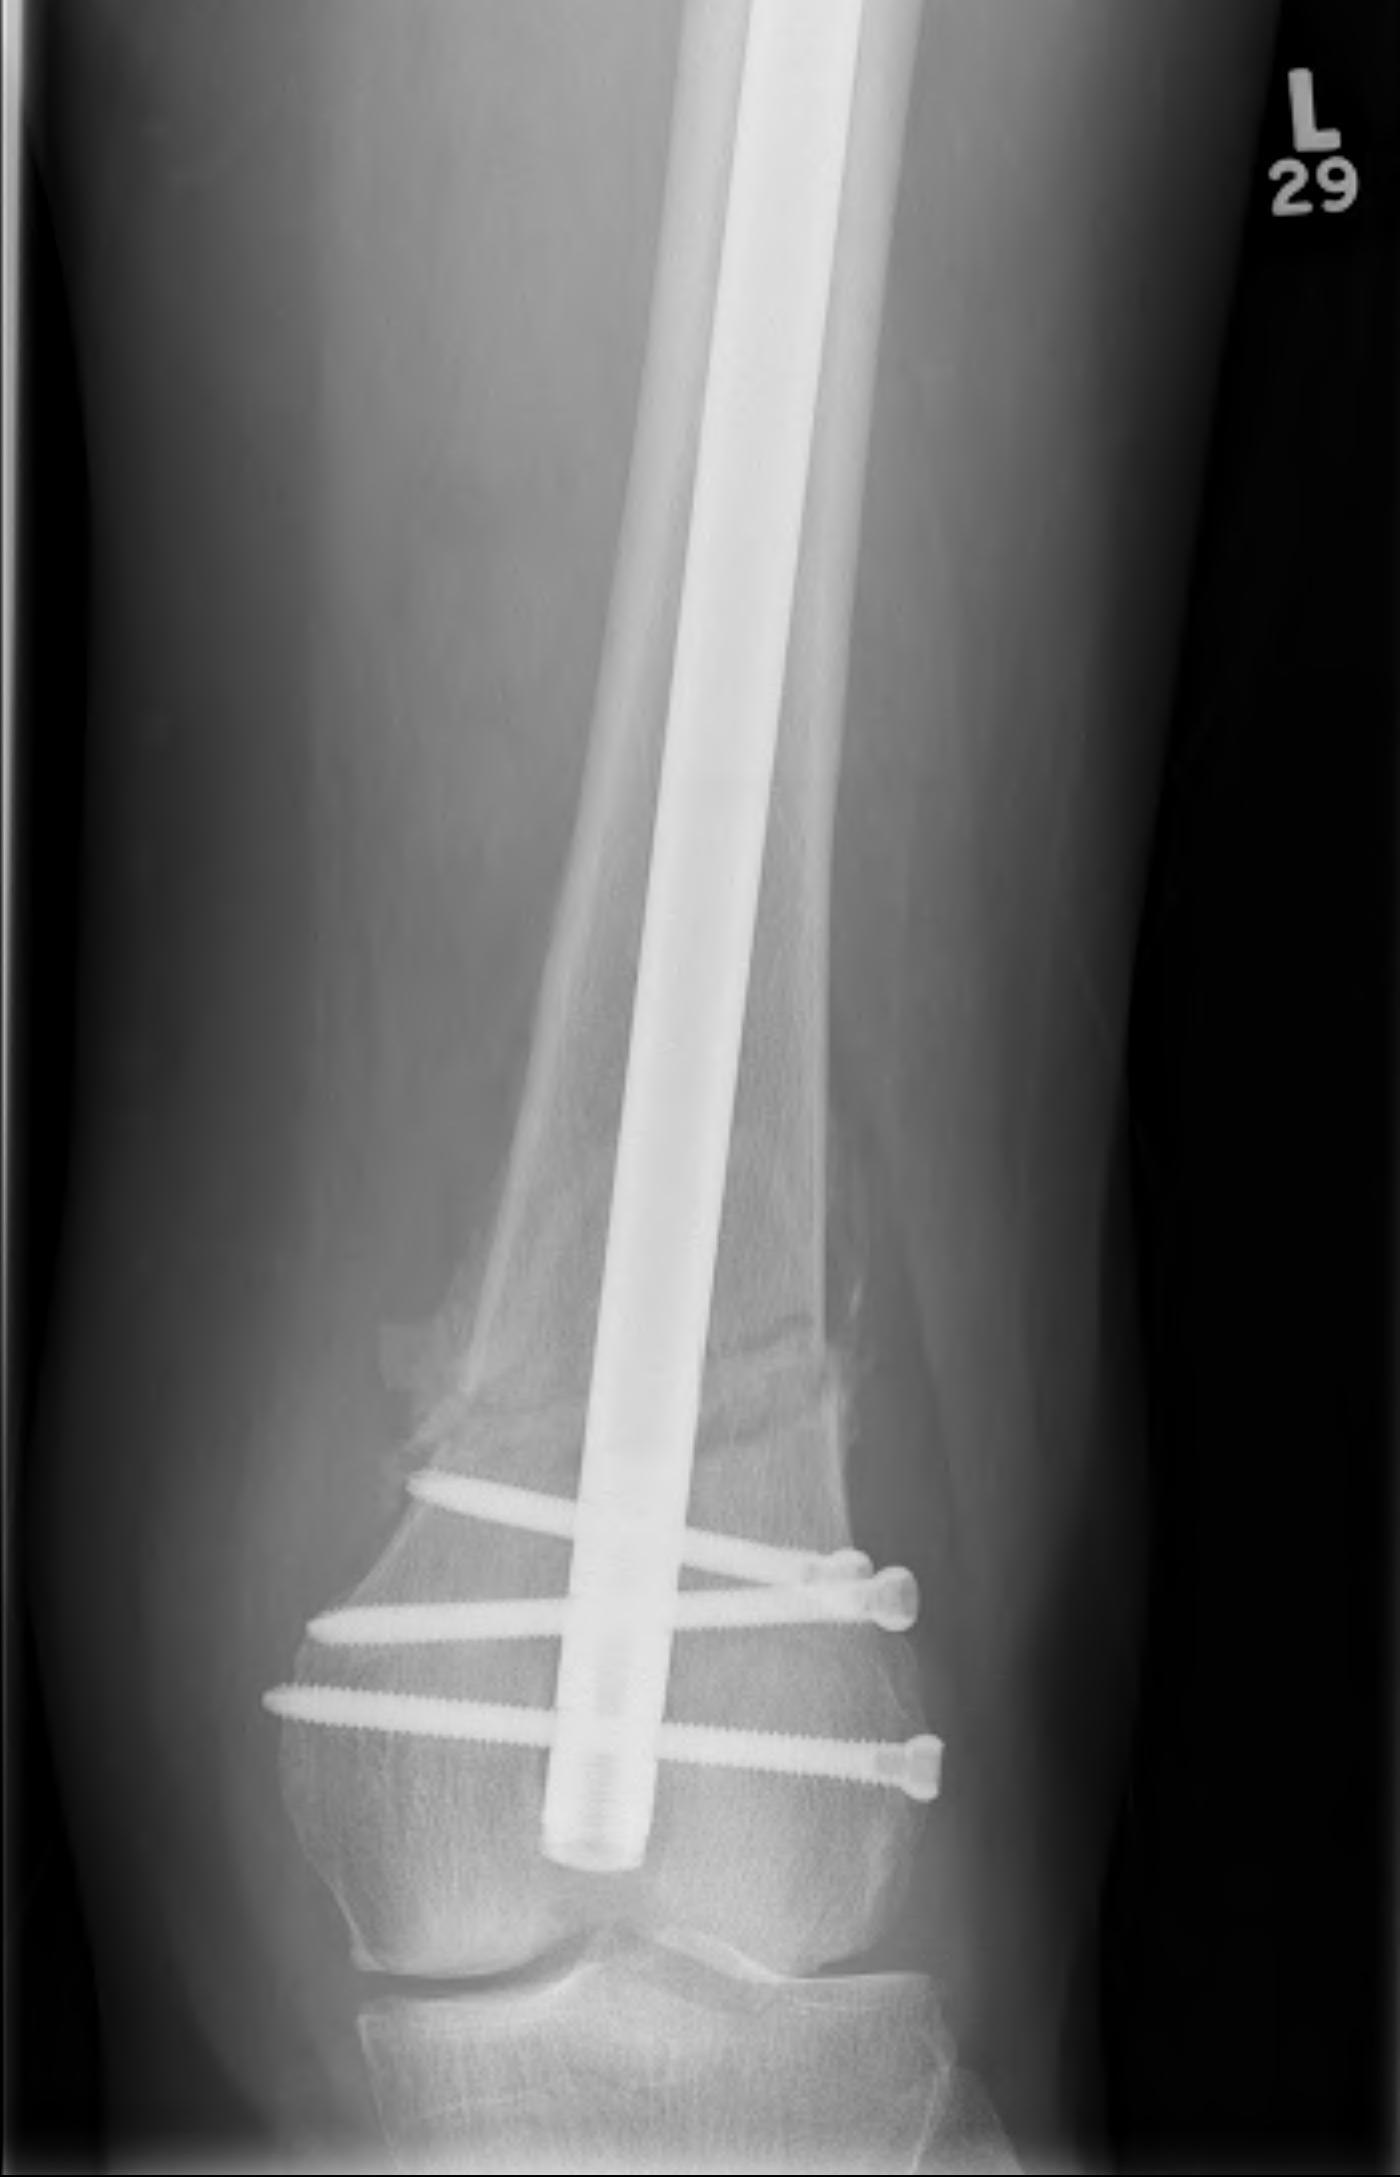

Nail

Iannacone et al J Orthop Trauma 1994

- 41 distal femur fractures treated with retrograde nail

- 4 non unions requiring revision fixation

- 4 fatigue fractures of the IMN; changed to using minimum 12 and 13 mm rods

Retrograde Nail

Surgical Technique

Pass guide wire

Locking screws

- distal locking performed with jig

- proximal AP locking under xray control